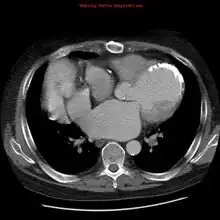

Transplanted heart in the thorax of recipient

CT chest: demonstrates the left anatomic connections in a heterotopic transplant